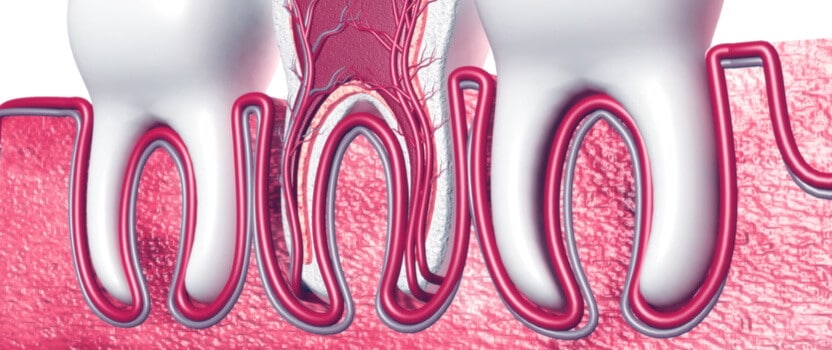

טכניקת מיגון מכתשית (Socket shield) להצלת העצם בלסת, עושה שימוש חכם בשיניים שנועדו לעקירה.

רופא השיניים לא עוקר לגמרי את השיניים אלא משאיר חלק מהשורש הטבעי של כל שן מחובר אל עצם הלסת.

הפעולה הזו גורמת לכך שהגוף “מזהה” חיבור של שורשי שן לעצם ומונע את ספיגתה חזרה ומצד שני מאפשר להשתיל מערכת שיניים חדשה בלי להשאיר שיניים חלשות בפה.

שורש העצם מעוגן אל תוך עצמות הלסת וחשוב מאוד למניעת ספיגת לגוף